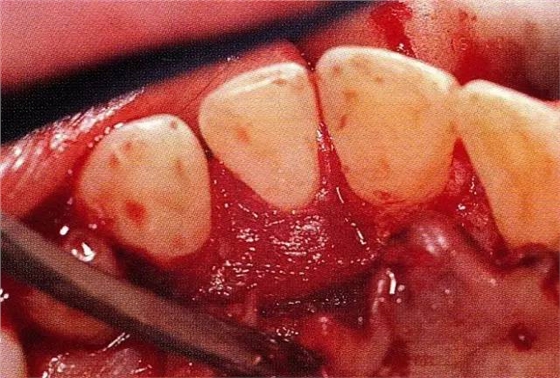

案例3針對(duì)3壁性垂直性骨缺損使用非吸收性膜進(jìn)行再生治療,再翻瓣時(shí)進(jìn)行骨形態(tài)修整的病例。

▲圖7-1左下6近中可觀察到3壁性垂直性骨缺損。此病例考慮到齦瓣供血關(guān)系,在前磨牙部位進(jìn)行了減張切開,沒有進(jìn)行縱切開。并利用刮治器、牙周外科用車針進(jìn)行了徹底的骨缺損部位搔刮。